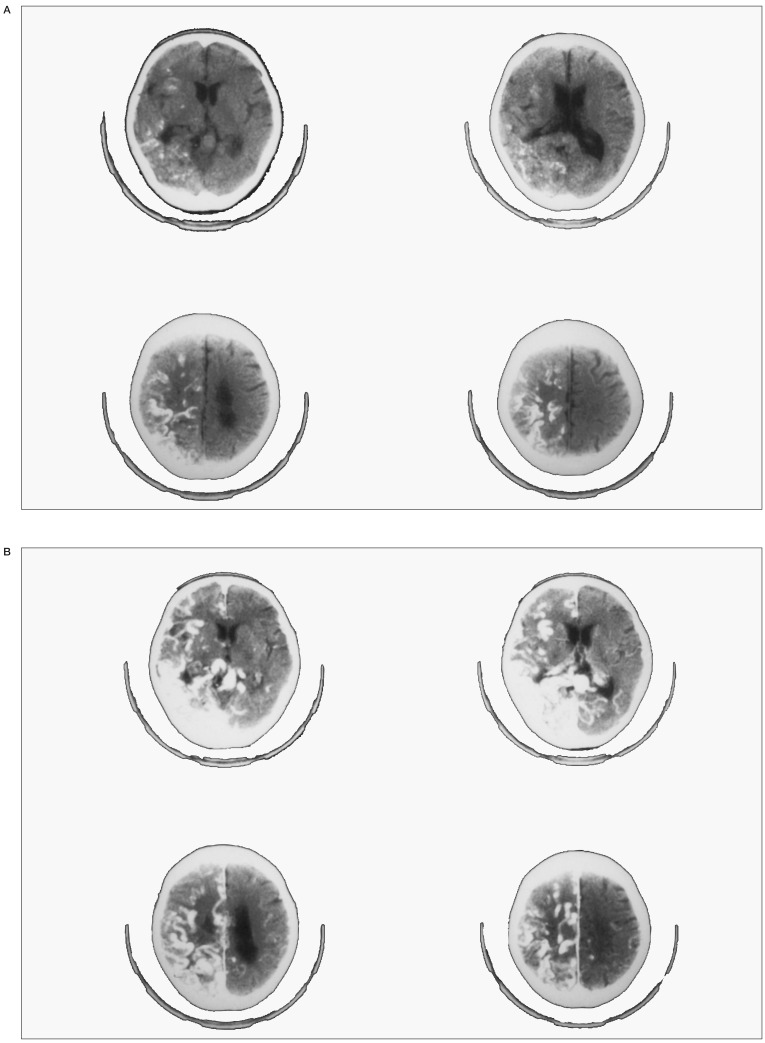

Figure 3.

(Case 3) - A,B) Left carotid angiography, AP and lateral projection demonstrating a massive insular AVM. Note prominent stagnation of contrast material in the basal vein of Rosenthal that is markedly dilated due to abundant flow from the nidus and stenosis in the Galenic-straight sinus junction. C,D: Left carotid angiography, AP and lateral projection after embolization. Note prominent reduction in size of the nidus and marked shrinkage of the tortuous basal vein. E,F: CT taken before (left) and after (right) embolization. Note that a huge varicose vein severely compressing the midbrain from laterally before embolization, dramatically lost mass effect to the brain stem after embolization. G: The patient's right arm showing a scar formed by wrist cut with suicidal intent. H) The patient at 6 month follow up after surgery showing only a mild right hemiparesis.

Right hemiparesis and hemihypesthesia became prominent 7 months prior to admission, emotional and urinary incontinence became prominent 6 months prior to admission, and the patient became aphasic 5 months prior to admission. After being divorced by her husband, she conducted a suicidal attempt in desperation (figure 3 G ). Disturbance of consciousness progressed further and she was comatose when the diagnosis of a massive cerebral AVM was made using CT two months later. In addition, the patient presented with conjugate deviation to the left, complete right hemiplegia and hemihypesthesia on admission. Cerebral angiography showed that the main feeding pedicles came from the insular segment of the middle cerebral arteries and the anterior choroidal artery. Interestingly, insular veins drained predominantly into the basal vein and caused marked enlargement and tortuosity of this vein (figures 3 A,B ). The posterior medial and lateral choroidal arteries, the anterior and middle temporal branches of the posterior cerebral arteries and the lateral striate arteries were also supplying blood to the AVM. CT showed that a huge varicose vein severely compressing the midbrain from laterally. There was no perinidal edema. As it was thought that the patient's cardinal neurological deficits were caused by mechanical compression to the upper brain stem by venous components and developed relatively recently, we expected that they may be reversible by embolization of the AVM. The main feeding pedicles were embolized in two sessions using EVAL. On completion of embolization, approximately 80% of the nidus was embolized. The embolization procedure brought about prominent decrease in degree of brainstem compression as a result of marked shrinkage of the nidus and the draining veins (figures 3 C,D,E,F). To our pleasant surprise, the patient showed spectacular recovery of disturbance in consciousness, right hemiplegia and aphasia shortly after the second session of embolization (figure 3 H).